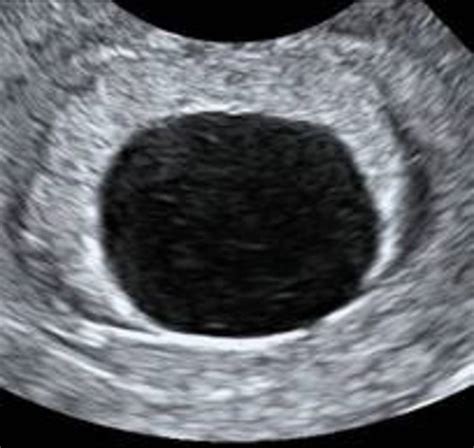

Diagnosing is almost forever support via transvaginal echography. A doctor will appear for the front of a gestational sac and, depending on the gestation period, look for the conceptus within that sac. If the sac is empty and measure a certain size, the diagnosing of a spoilt ovum is confirmed.